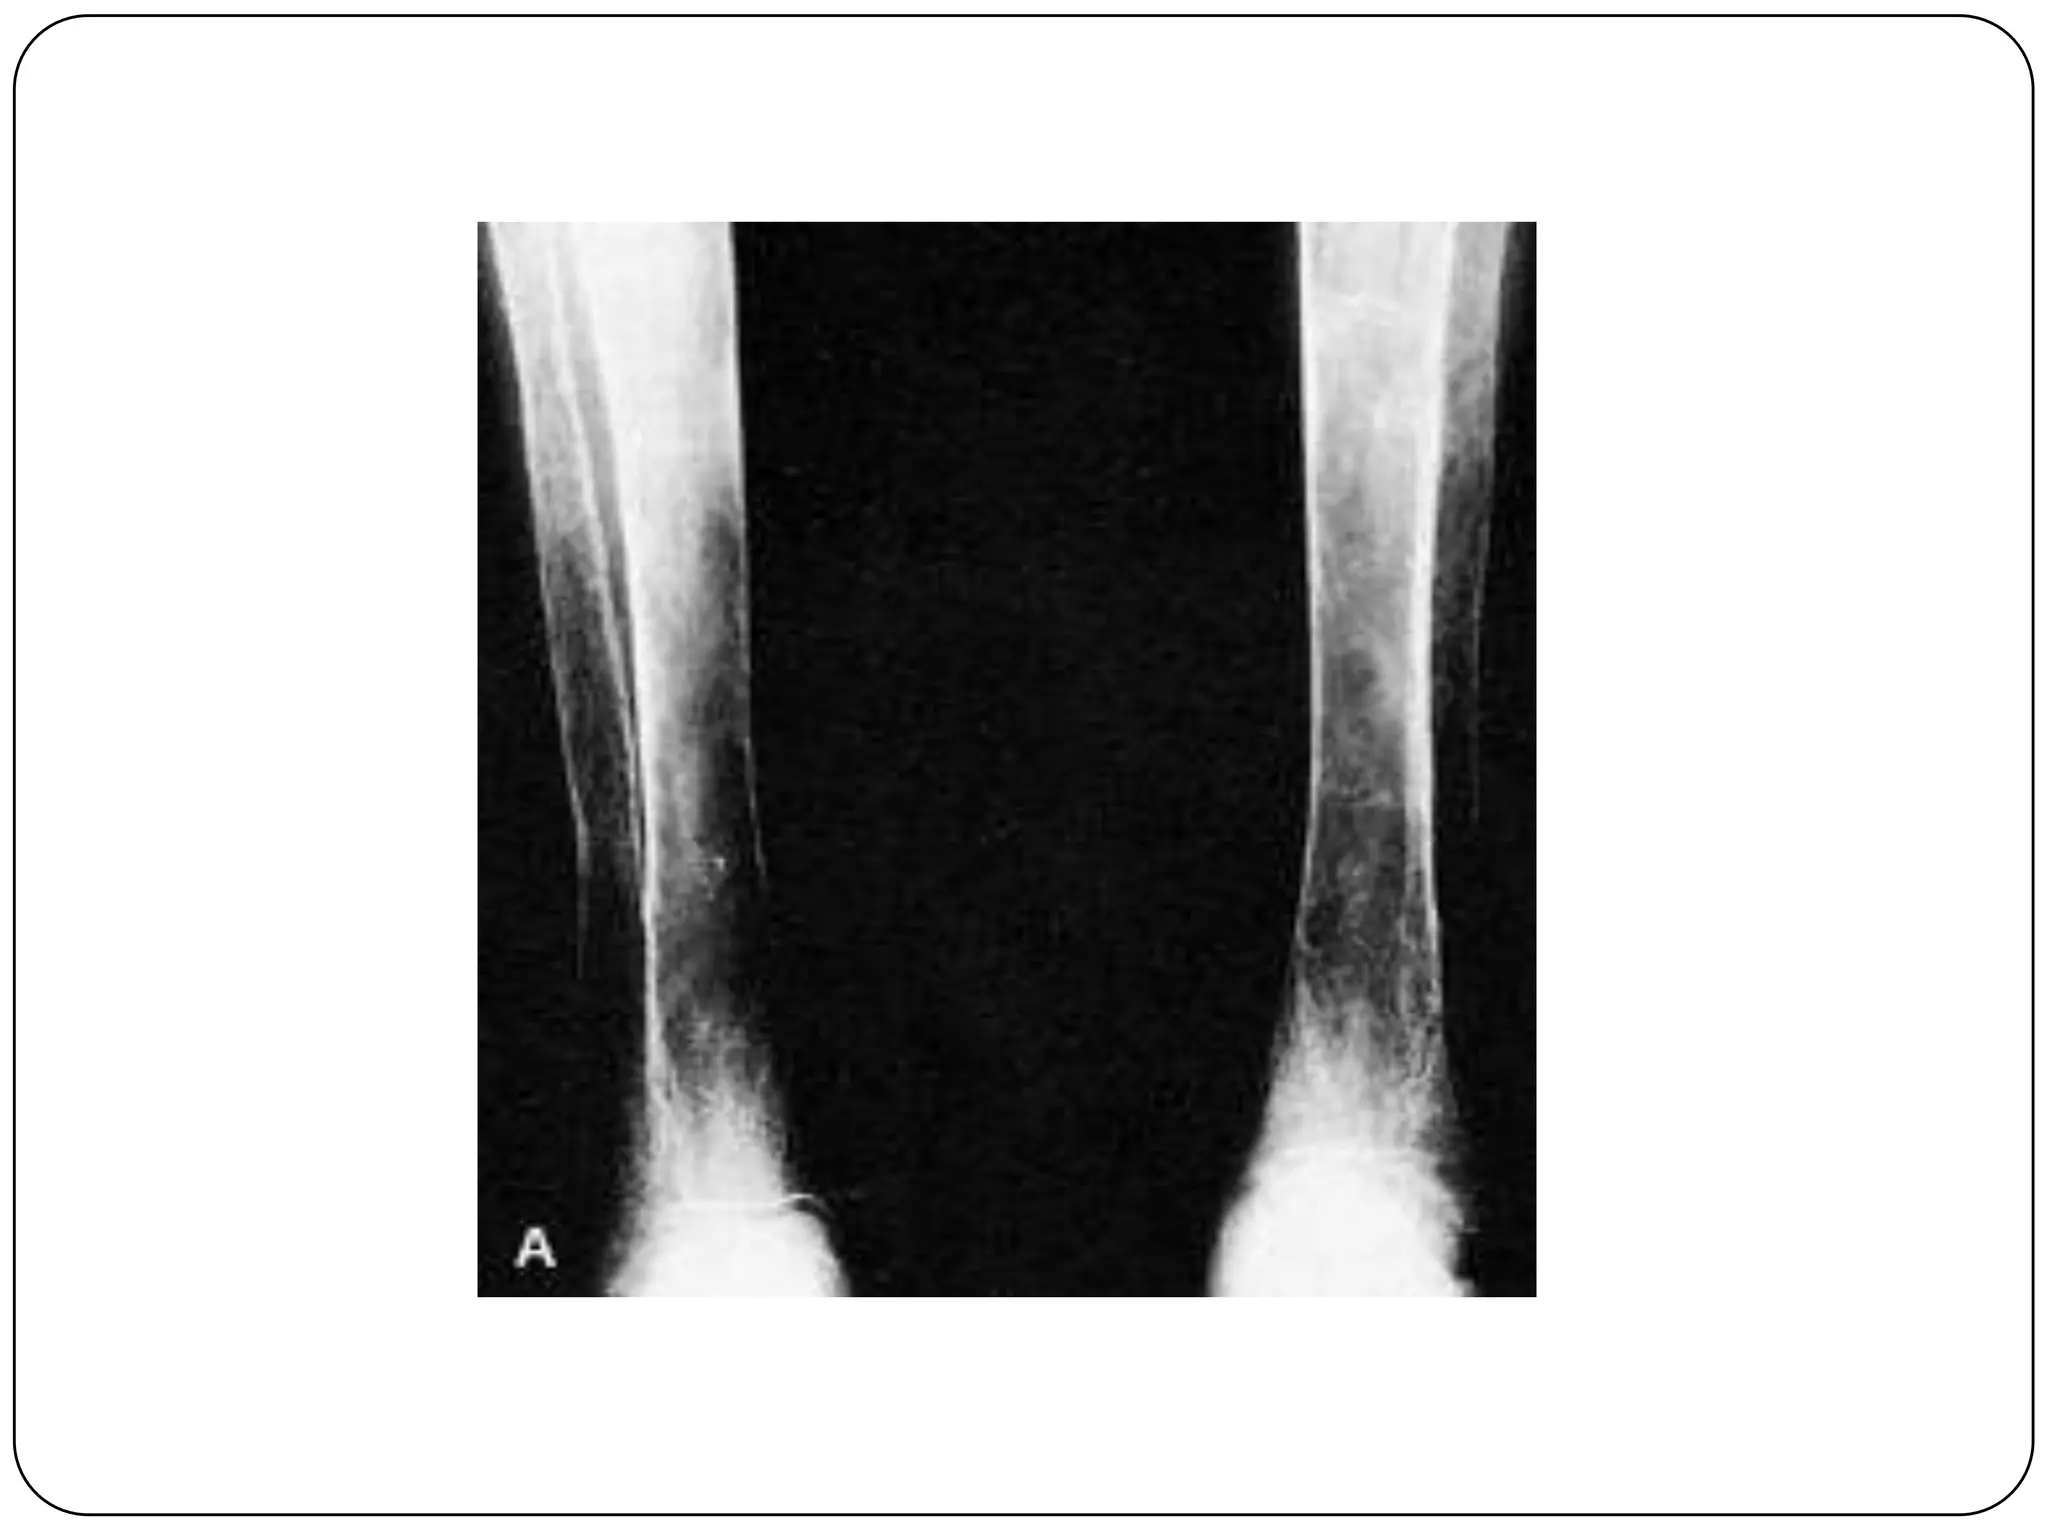

   6.X- ray- bone marrow hyperplasia

Hair on end sign